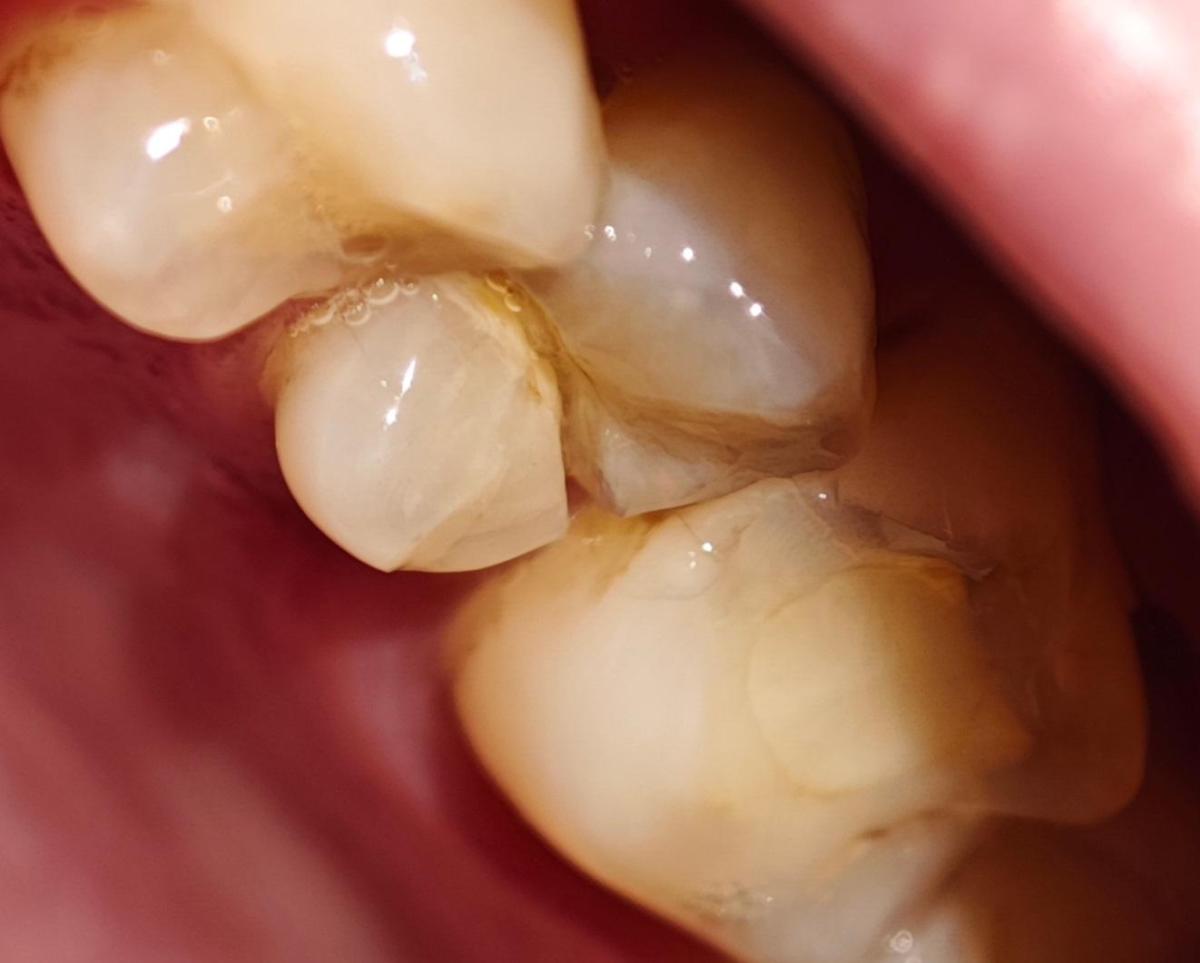

И буквально 2 дня назад, сидя смотря фильм, я почувствовал, как будто по зубу что-то ударило, сначала не придал значения, потом языком нащупал странность, зуб как будто стал шире и появилось что-то лишнее (не знаю, как правильно это выразить).

Ну и пошёл сделал фото под макросъёмкой, и увидел то, что его часть лопнула и он реально стал шире.